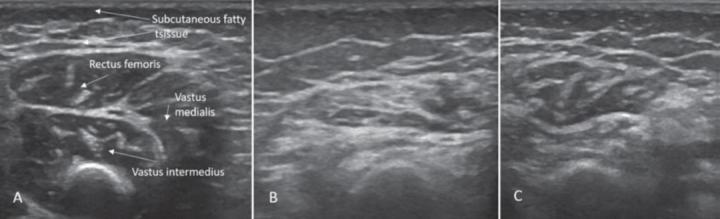

image: Sonographic findings of quadriceps in child diagnosed with SMA: (A) Age 2 months: normal echogenicity and clearly visible internal septa. (B) Age 14 months, 6 months after onset of disease: a pathologic increase in background echogenicity in comparison to subcutaneous fat tissue and less definable intramuscular septa. (C) Age 17 months, after eight months of nusinersen therapy: partial recovery with increase in volume and normalization of echogenicity in the rectus femoris.

One specific case in the German study concerned a child in whom the SMN2 copy number was intially incorrectly reported as high and treatment thus not initiated. The child then developed symptoms of SMA at eight months of age. After onset of symptoms, it took another five weeks until the insurance company approved treatment. During the delay, the child continued to deteriorate until he was unable to bear any weight on his legs. Once treatment began, the child partially recovered. "We assume early treatment prevents or limits damage to motor neurons, helps recovery, and prevents progression, thus arguing for the earliest possible treatment," commented Prof. Dr. Müller-Felber.